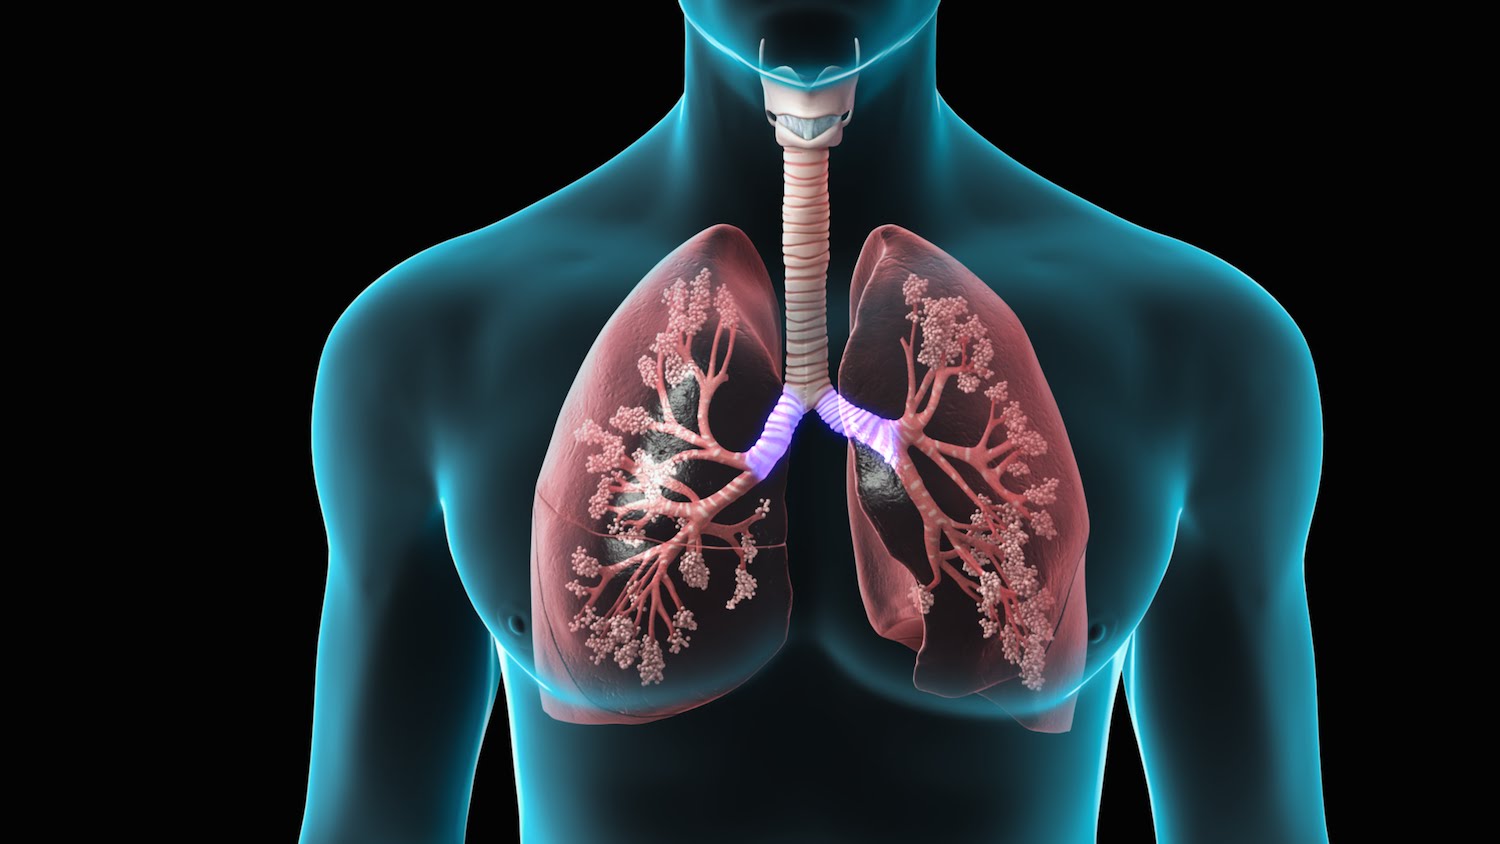

Over the decades, Cancer has become one of the major causes of deaths. Out of 8 major types of cancer, lung cancer is one of the most widely spread cancer which kills the maximum number of people each year, which includes both men and women around the globe. We all have heard of examples where cancer patients are cured, however, the number of people dying from it is rapidly increasing.

You’ll be surprised to know that lung cancer existed much before cigarettes came in trend. When there was almost no pollution compared to today’s date. The first case of lung cancer was recorded in 1761. But those days, only people with multiple health issues used to have it. Also, it is assumed that lung cancer only affects the lungs, when in reality this disease can spread across the body in a process called metastasis which means tumors can spread to the brain and can cause loss of vital functions e.g. vision.

Cigarette smoking is the most common reason that increases the risk of lung cancer. Not only for those who smoke but for those who are passively exposed to tobacco smoke have almost equal chances of lung cancer. These two are the main reasons behind lung cancer.

Yes, smoking is the major cause of lung cancer. However, neither every smoker has lung cancer nor lung cancer occurs only in smokers. “In nonsmokers, radon exposure is thought to be a major preventable cause of lung cancer,” stated Mara Antonoff, MD, a thoracic surgeon and assistant professor at the University of Texas MD Anderson Cancer Center in Houston.

Not every smoker and passive smoker develops lung cancer and there are patients who never did tobacco smoking and still have the disease which leads to the question; what actually causes this killer disease?

We all inherit certain genes and when genes intervene, DNA repair it brings people under higher risk for not only lung cancer but several types of cancer. There’s no certainty about it though, it’s been said that lung cancer can be caused due to individual’s genetic sensitivity. So far, there is no test to identify the increased genetic risk of cancer for conventional use.